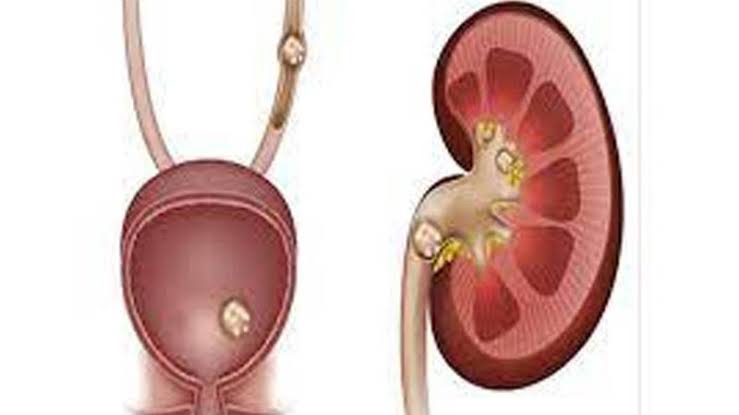

وأوضح أن الحصى عادة ما يتكون في تجويف الكلى، ولكن في حالة تصدعها تسقط داخل الحالب، مما يسبب آلاما حادة لا تحتمل.

- وفي حالة سقوط الحصى في الحالب فإن الشخص يشعر بألم حادة تصل إلى مستوى الشدة.

وأشار إلى أن في حالة استمرار الالم لعدة أسابيع، أو في حالة ظهور الحصى في حجم كبير، يلجأ الطبيب إلى عملية استئصال الحصى أو تفتيتها.

ونوه إلى أن تقنية استئصال الحصى تختلف وفقا لنوع الحصى وأيضا لحجمها، وأماكن وجودها.